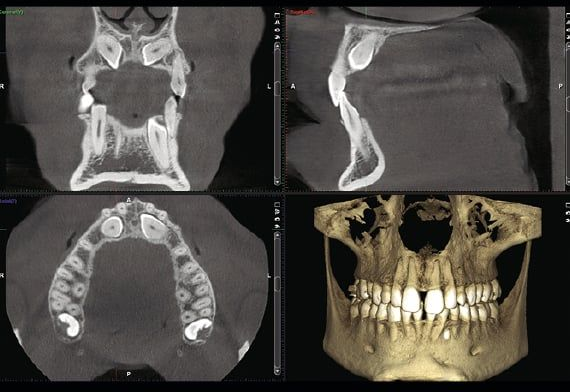

Planmeca

Radiografia panoramica delle arcate dentarie.

TC Cone Beam

Con questa apparecchiatura vengono eseguiti gli esami 3D delle arcate dentarie.